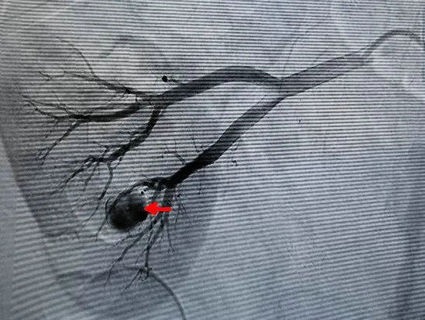

▲ 左图红色箭头为肾动脉分支动脉瘤,右图红色箭头为栓塞治疗后效果

时间就是生命,在吕军主任医师的指导下,通过术中肾动脉造影,发现肾动脉分支动脉瘤,找出了问题所在,微导管到位、颗粒栓塞一气呵成,病人血尿颜色变淡,手术治疗取得圆满成功。根据术后随访,杨大哥未再出现血尿,并已于近日出院。